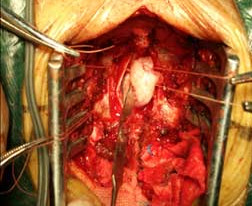

椎管内肿瘤 椎管内肿瘤术中